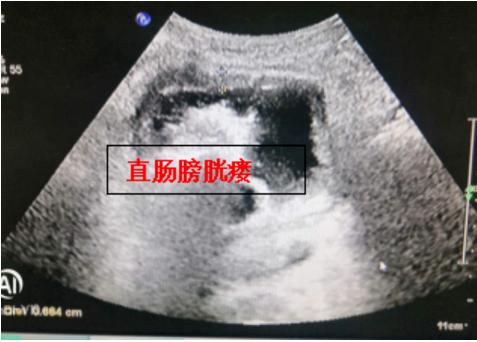

考虑到患者病情危重,刘汉博主任当即安排科内胡石甫主治医师负责该患者的诊疗。当天下午患者入住普通外科病房,胡石甫医生迅速完成患者全身器官功能评估:一方面是肿瘤外科急腹症-直肠肿瘤几乎完全堵塞肠管已经造成低位肠梗阻;另一方面,晚期直肠癌局部侵犯膀胱后壁形成直肠膀胱瘘,膀胱内大量粪水成分;此外,患者长期肿瘤消耗,营养状况不良合并急性感染,诸多不利因素集于一身,病情复杂。

接下来通过近5天的抗炎+肠外营养+膀胱持续冲洗治疗后,患者机体较前明显改善。胡石甫医生再次尝试超细内镜下明确瘘口状态,通过反复盐水冲洗梗阻近端后,终于精准测量出肿瘤病变长度,同时完整显露膀胱后壁瘘口全貌,“直肠肿瘤全腔狭窄病变长径6cm,直肠膀胱瘘口大小约4cm*3cm,近1/3圈直肠前壁缺损,瘘口周围肠壁因为放疗呈大范围的糜烂充血水肿改变”。